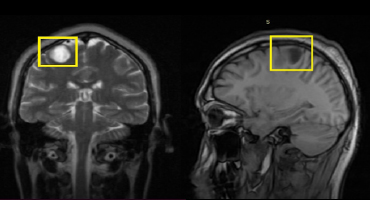

NEUROCISTICERCOSIS

Resonancia Magnética